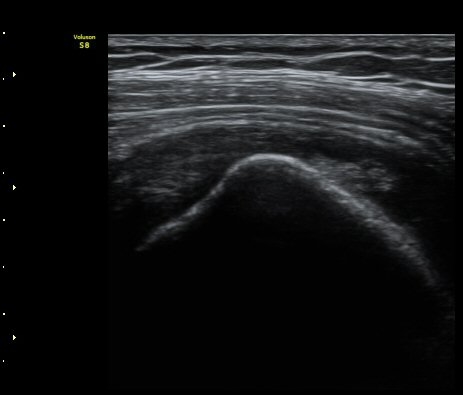

°Ë»ç¿¡¼­ Ç÷·ùÁõ°¡´Â °üÂûµÇÁö ¾Ê´Â´Ù(±×¸² 1, 2).   À̵ιڱ٠¾Æ·¡ Ⱦ´Ü¸é°Ë»ç¿¡¼­

°üÀý³» ¼ö¾×Àú·ù´Â ¶Ñ·ÈÇÏÁö ¾Ê´Ù(±×¸² 3). ±Ø»ó°Ç Á¾´Ü¸é°Ë»ç¿¡¼­ Á¡¾×³¶³» ¼ö¾×